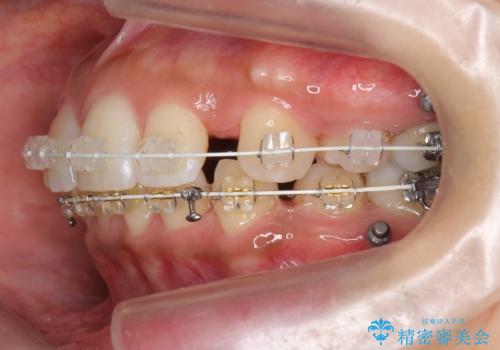

- 矯正装置

- 審美装置

- 治療計画

- 前歯を下げたいと来院。

初めは、上だけ抜歯しましたが、もう少し口元を下げたいとのことで追加で下顎を抜歯しました。

年齢の割に歯が動きにくかったこともあり、また、追加で抜歯して結果として時間がかかってしまいました。口元が大きく下がり、結果には満足していただけました。